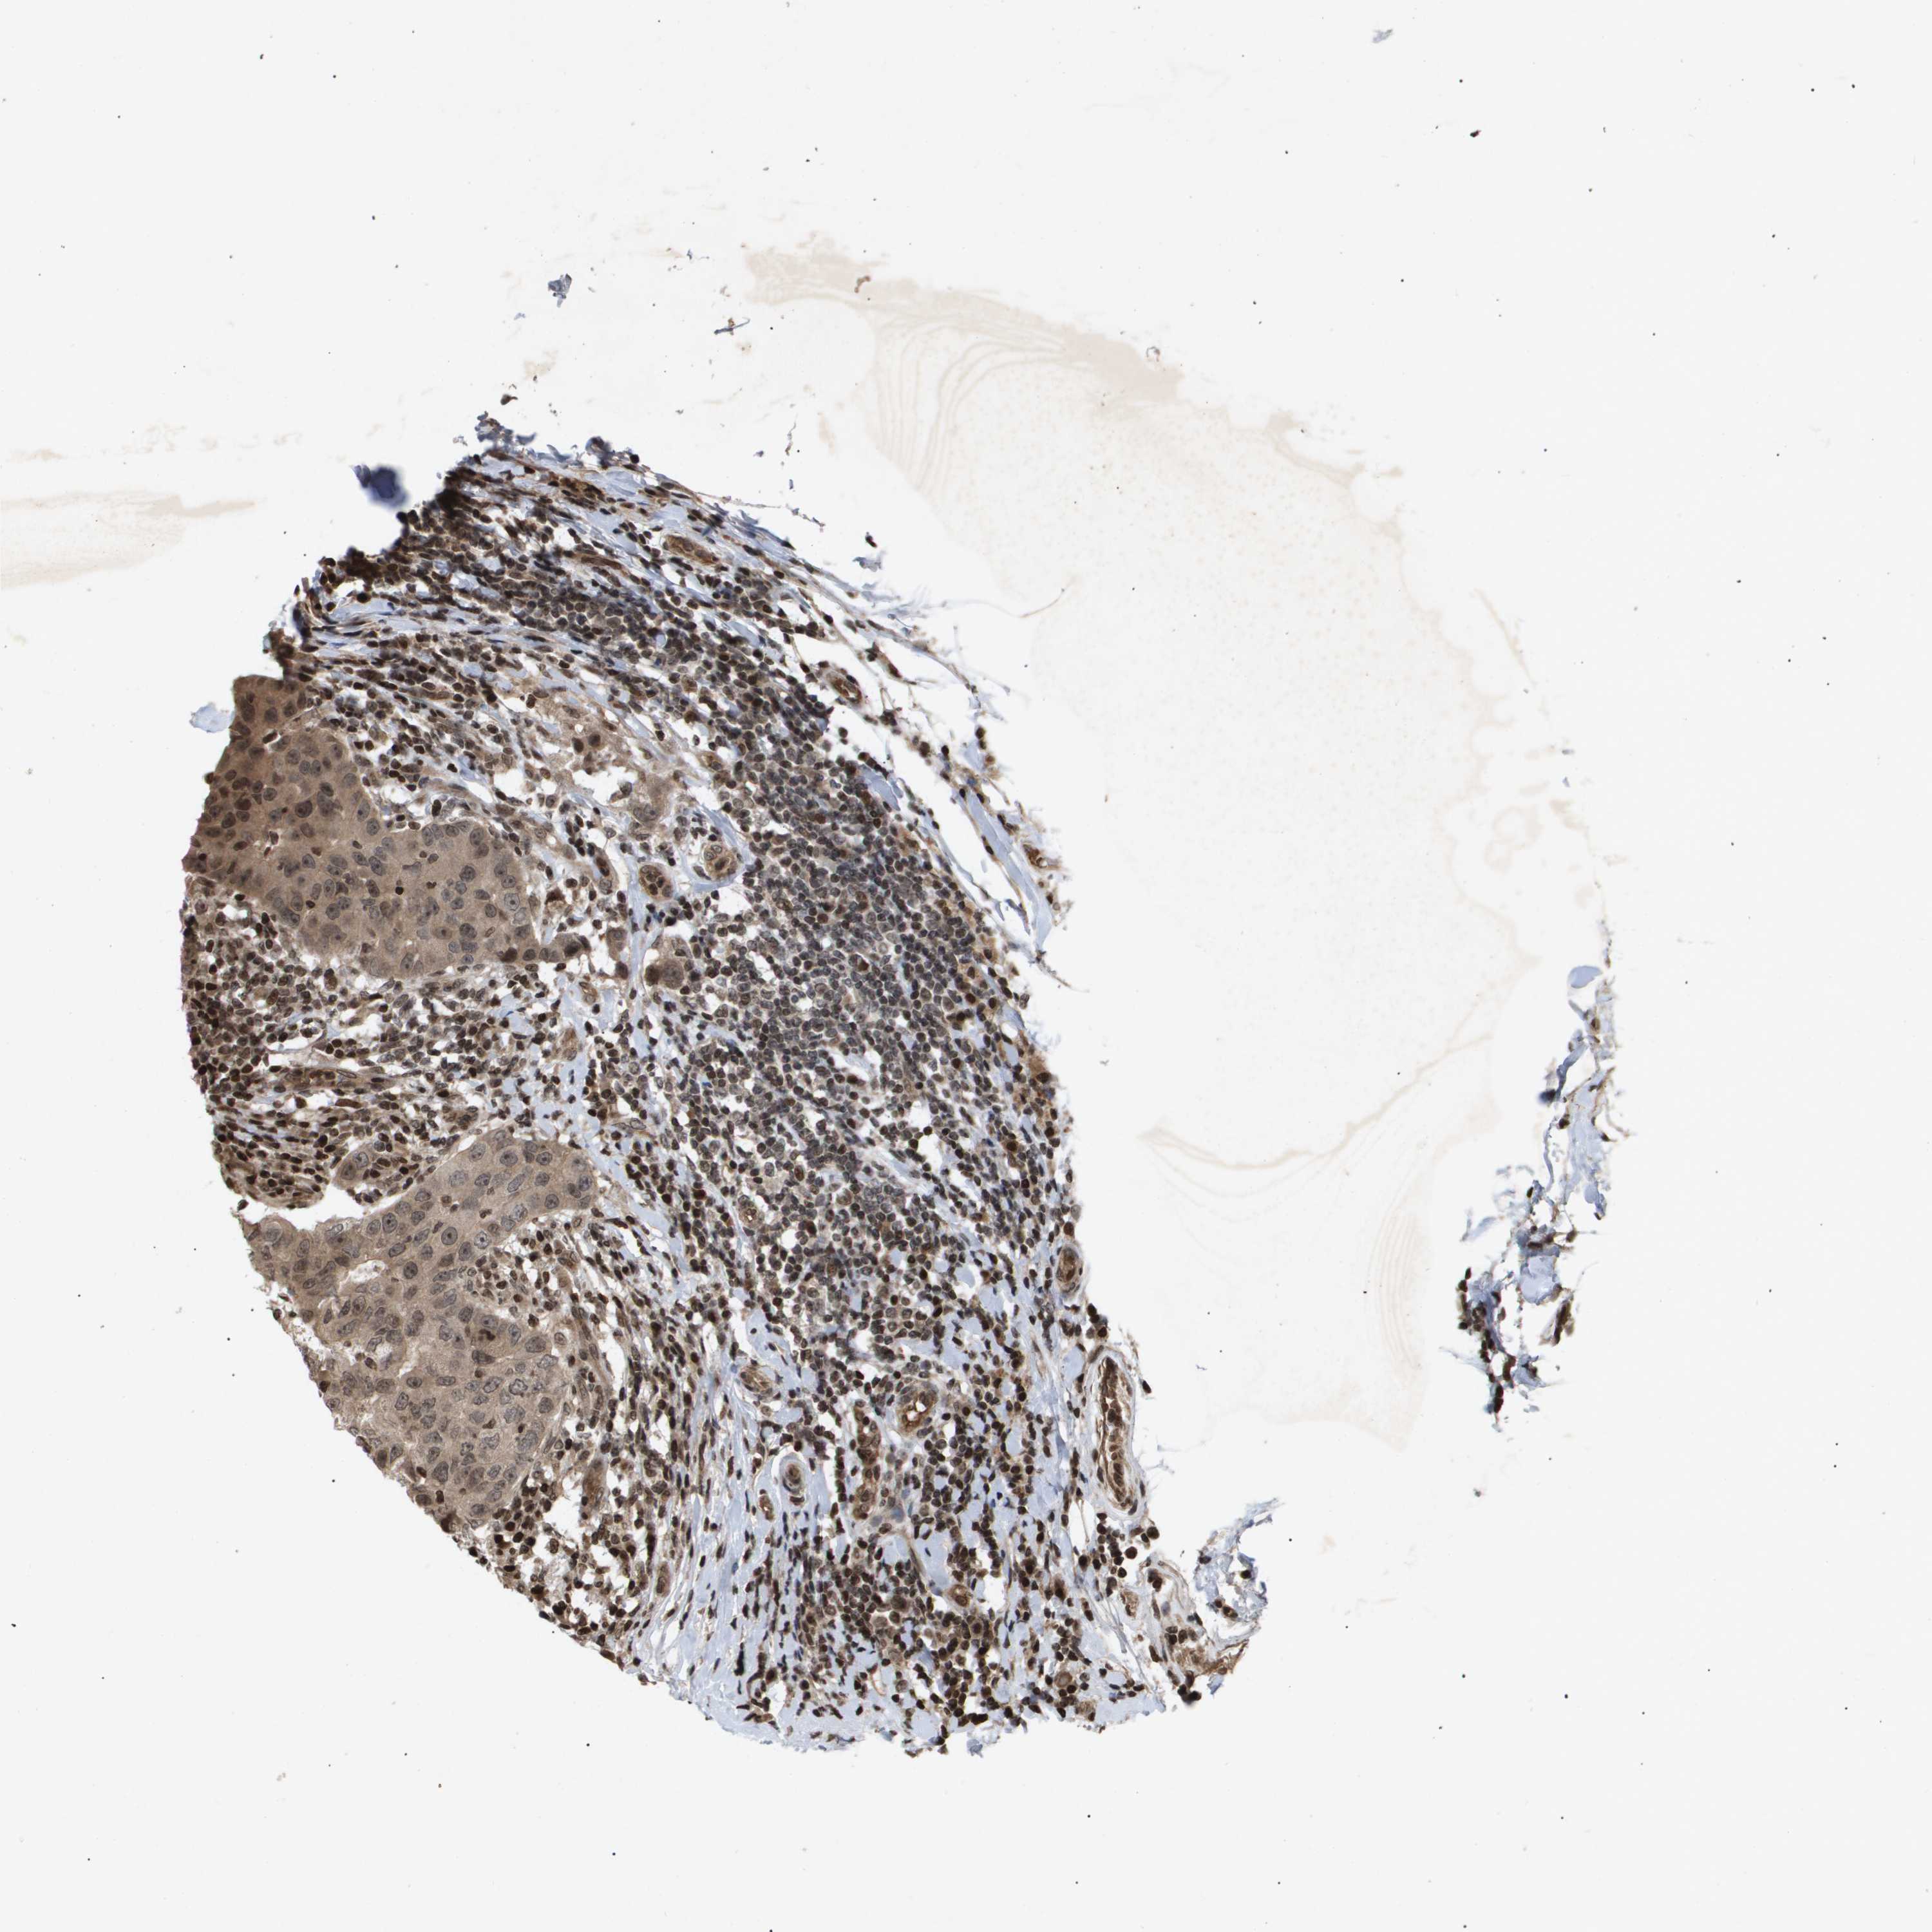

CANCER BREAST CANCER Show tissue menu

BRCA TCGA BRCA VALIDATION PROTEIN EXPRESSION